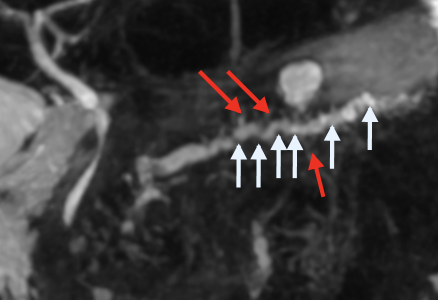

IRM

- T1 FS: Le pancreas sera plus hypo que le foie (plus hyper normalement)

- Irrégularités du Wirsung

- Atrophie de la Glande

- La Diff n’aide pas

- Cancer à chercher, dur a différencier de la pseudomasse inflammatoire, chercher les signes indirects type dilatation canalaire majorée)